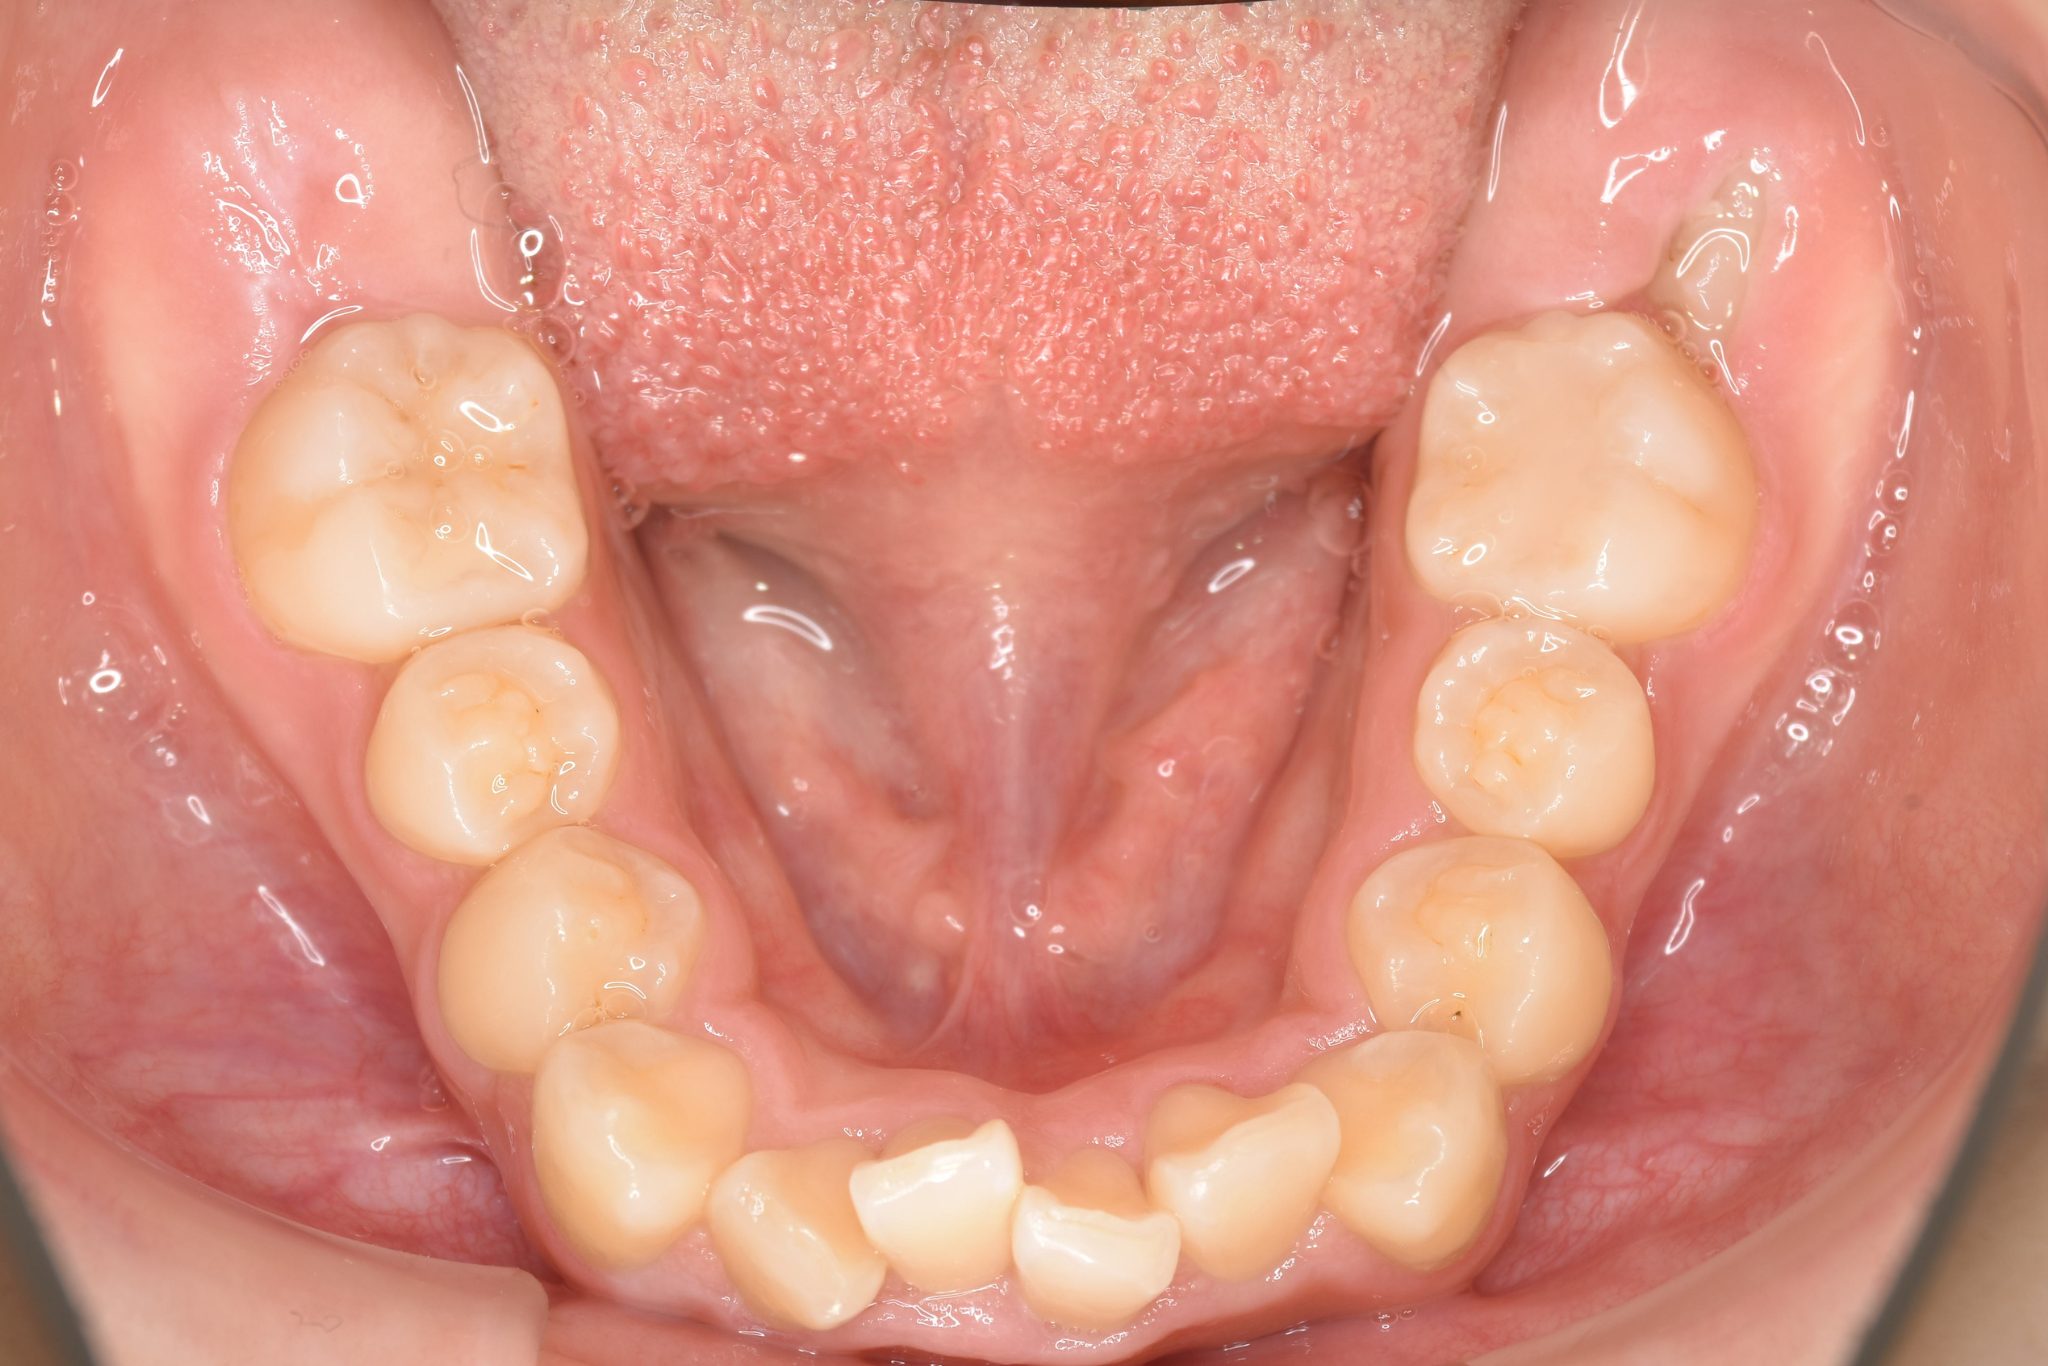

ビフォー

ワイヤー矯正治療|症例_349

主訴 下の前歯が見えない|歯がガタガタ

施術内容 MSEと下顎リンガルアーチを用いて上下顎骨を拡大した。

その後マルチブラケット装置を用いて非抜歯で歯牙を配列し、良好な咬合を獲得した。